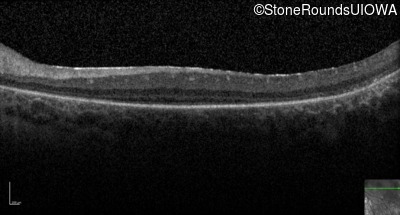

Optical Coherence Tomography - Right -

No Light Perception

Exemplar

Expanded OCT Stack

×

Optical Coherence Tomography - Left -

Light Perception